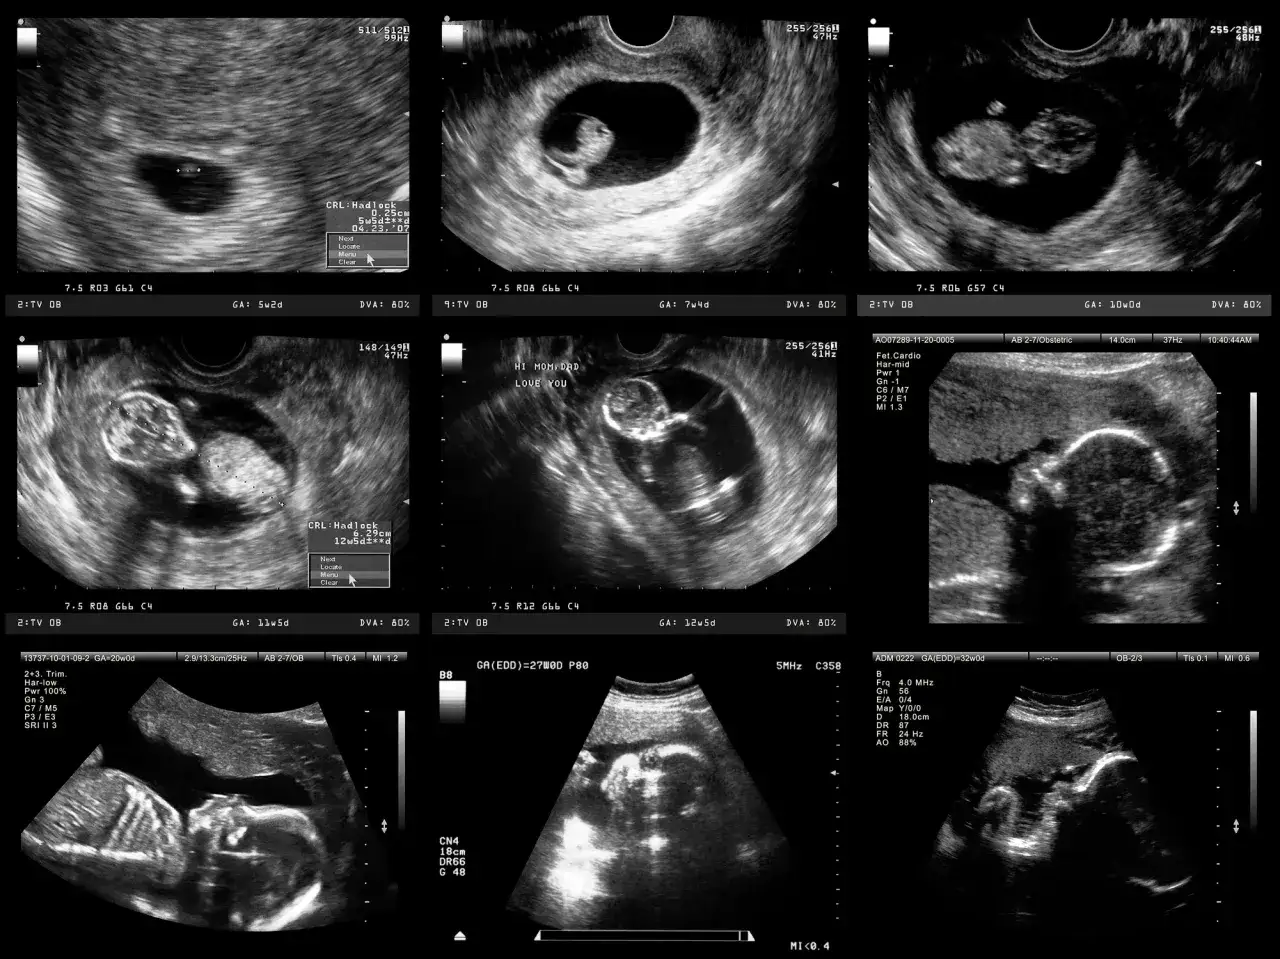

USG połówkowe (18-22 tydzień): Najdokładniejszy przegląd zdrowia Twojego dziecka

USG połówkowe, nazywane również morfologicznym, to bez wątpienia najważniejsze i obowiązkowe badanie w drugim trymestrze ciąży. To moment, w którym masz szansę na bardzo szczegółowe spojrzenie na rozwijające się dziecko, a lekarz może ocenić jego anatomię z niezwykłą precyzją. Dla wielu rodziców to także wzruszająca chwila, gdy mogą zobaczyć swoje maleństwo w pełnej krasie.

USG połówkowe jest wykonywane w ściśle określonym przedziale czasowym między 18. a 22. tygodniem ciąży. Ten termin nie jest przypadkowy. W tym okresie wszystkie organy płodu są już na tyle rozwinięte i osiągnęły odpowiednie rozmiary, że lekarz może je dokładnie zwizualizować i ocenić. Jednocześnie dziecko ma jeszcze wystarczająco dużo miejsca w macicy, co ułatwia przeprowadzenie kompleksowej analizy jego anatomii. Wykonanie badania zbyt wcześnie lub zbyt późno mogłoby utrudnić precyzyjną diagnostykę.

Podczas USG połówkowego lekarz przeprowadza niezwykle dokładny przegląd całego ciała dziecka. To prawdziwa "lupa" na rozwijający się organizm. Celem jest wykrycie ewentualnych wad wrodzonych, a prawidłowo wykonane badanie może je zidentyfikować aż w 90% przypadków. Oto, co jest oceniane krok po kroku:

- Ocena szczegółowej anatomii płodu (mózg, serce, nerki, płuca, kończyny, kręgosłup, twarzoczaszka).

- Ocena łożyska i jego położenia.

- Pomiar ilości płynu owodniowego.

- Ocena masy płodu i tempa wzrostu.

- Określenie płci dziecka (na życzenie rodziców).

Lekarz sprawdza symetrię i prawidłową budowę poszczególnych struktur, upewniając się, że wszystko rozwija się zgodnie z normą.